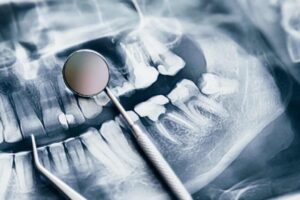

- Consulta inicial: Evaluación del estado de la salud bucal y identificación de problemas.

- Eliminación del sarro: Uso de ultrasonido o herramientas manuales para eliminar el sarro.

- Pulido dental: Suavizado de la superficie dental para prevenir la acumulación de placa.

- Aplicación de flúor: Fortalecimiento del esmalte dental.

- Instrucciones de higiene oral: Consejos personalizados sobre cepillado, uso de hilo dental y enjuague bucal.